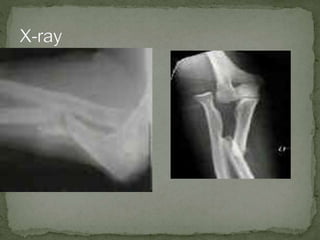

A 21-year-old female presented to the emergency department after a motor vehicle collision with left arm pain from striking the steering wheel without restraints. Examination revealed a swollen and deformed left upper extremity without open fracture. The arm was reduced and splinted, with the radial head gently repositioned anteriorly and the ulnar shaft reduced by manual pressure. Orthopedics was contacted to discuss urgent operative repair for a Monteggia fracture dislocation of the left forearm.